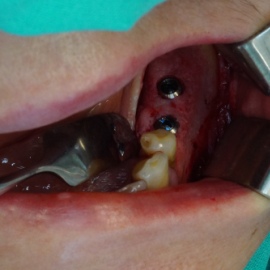

Pacjentka lat 72, od kilkudziesięciu lat chorująca na cukrzyce I typu, obecnie od 10 lat na pompie insulinowej. Profesor medycyny, siostrzenica pacjentki prowadzi swoją ciocię diabetologicznie, pacjentka świadoma zagrożeń przy zabiegach regeneracji kości i implantacji w takim ogólnym stanie zdrowia. Po rekonstrukcji tkanek miękkich i kości osadzono dwa implanty o średnicy 5,0 mm. Na zdjęciu śródzabiegowym widać zadowalające wyniki rekonstrukcji tkanki kostnej. Po upływie kilku miesięcy wykonano nadbudowę protetyczną.